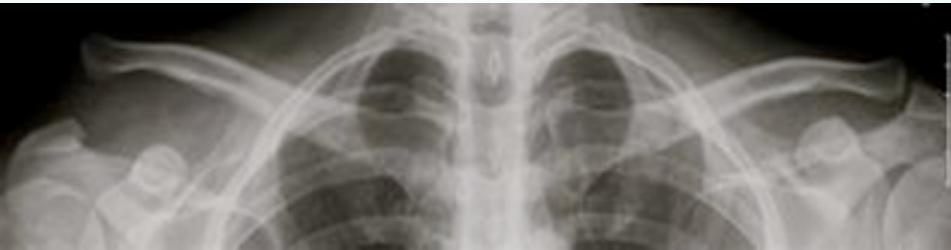

X-rays:

- AP (& lateral scapular) views

- Overlapping shadows of humeral head and glenoid

- Humeral head lies below and medial to glenoid

Important: Rule-out greater tuberosity fracture